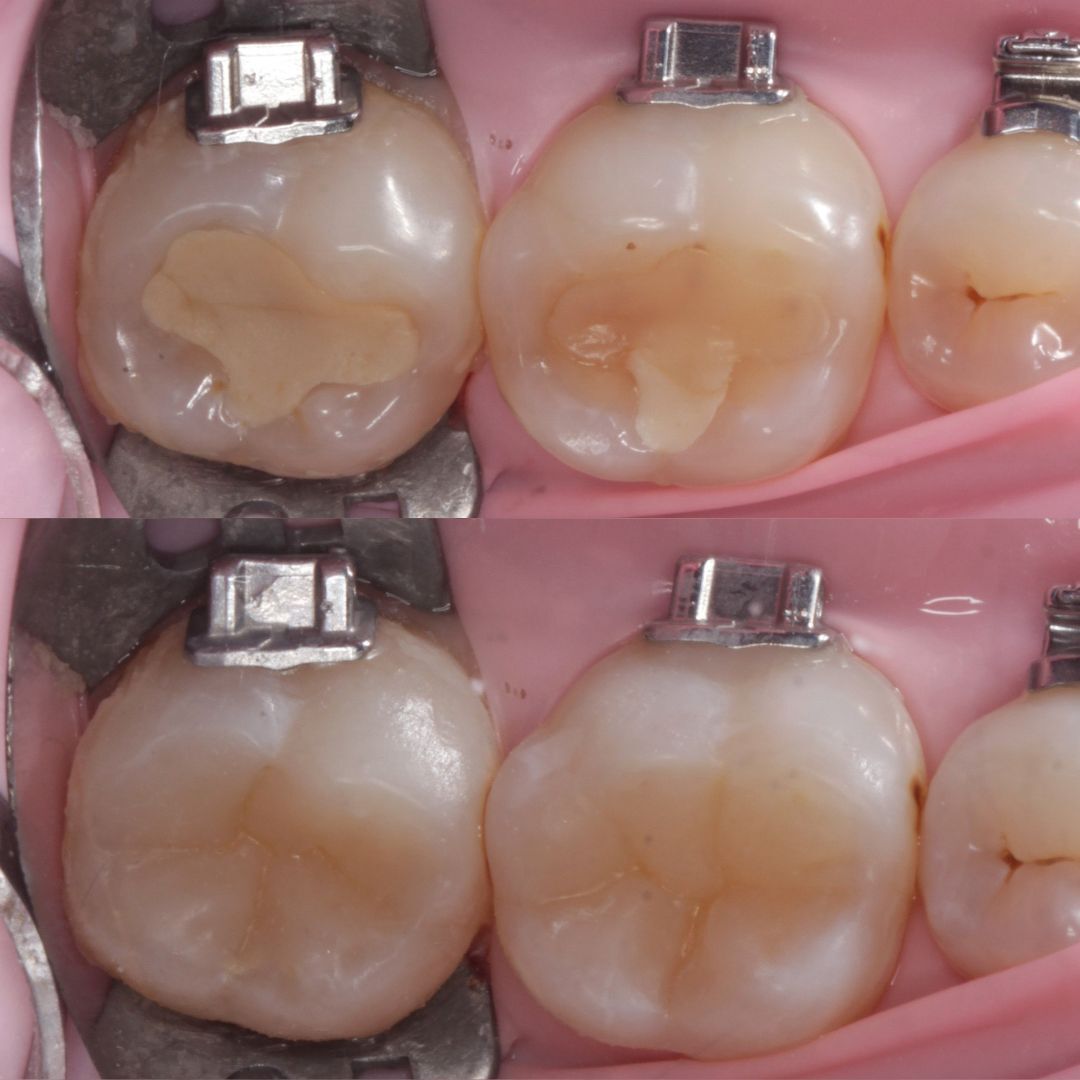

- Лечим зубы БЕЗ снятия брекет-системы

- Аккуратно обходим замочки и дуги

- Восстанавливаем анатомию зуба так, чтобы не мешать перемещению